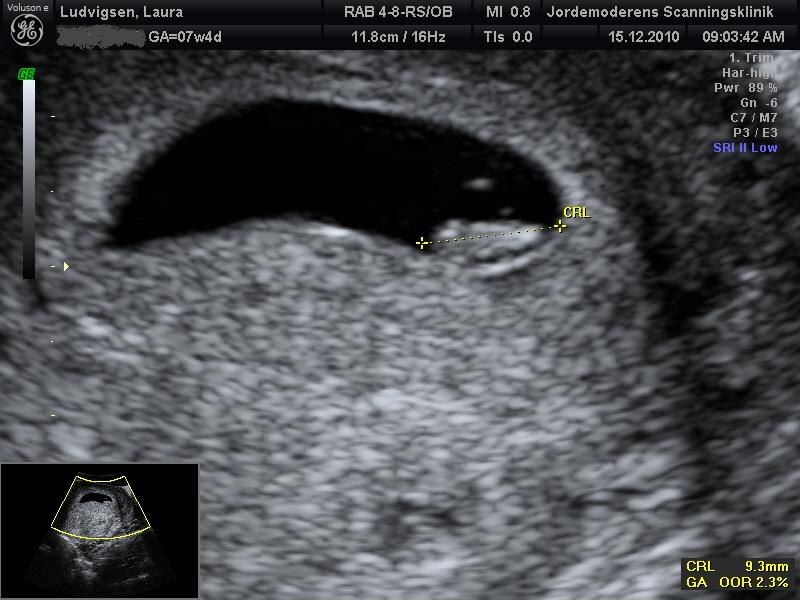

SCANNINGEN GIK SKIDE GODT.. 7+2 var jeg hjerteblink og ALT så godt ud.. masser af billeder + en Cd

Vedhæftede fotos (klik for at se i fuld størrelse)